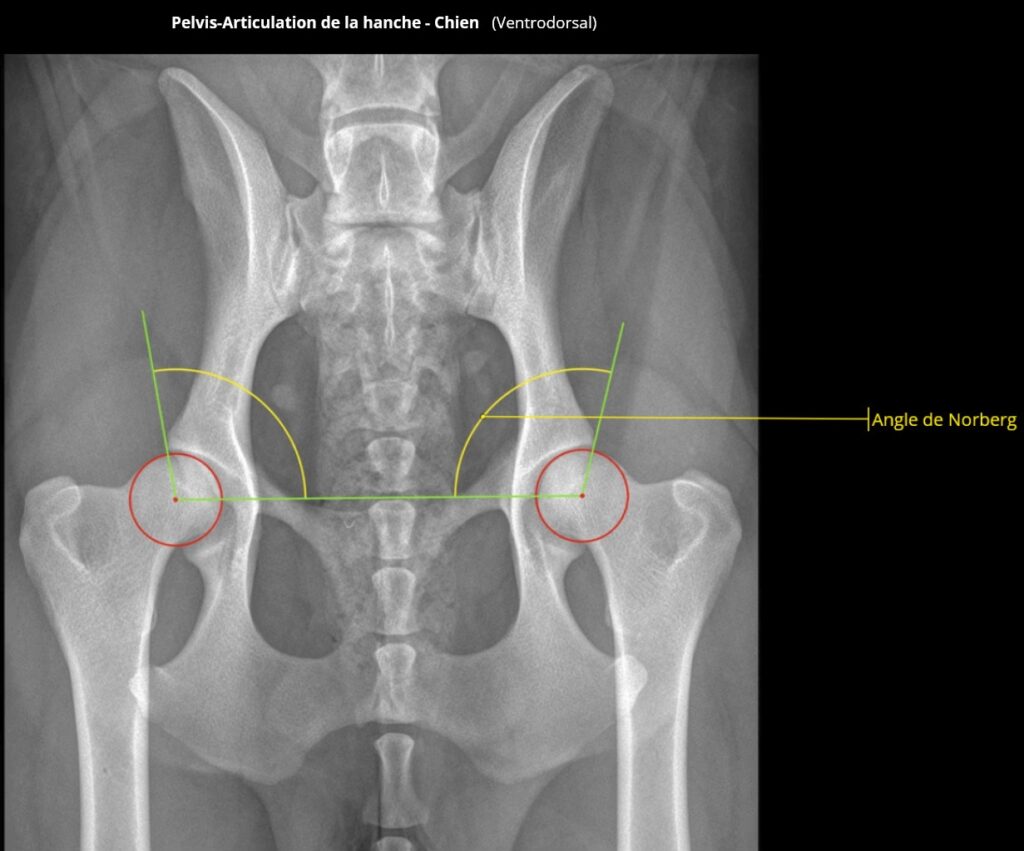

L’examen radiologique permet de mettre en évidence des signes d’arthrose ainsi que de mesurer l’angle de NORBERG-OLSSON, qui donne une idée de la couverture de la tête par l’acétabulum et de la pénétration de la tête au fond de la cavité acétabulaire.

Voir ci-dessous quelques clichés où l’angle de NORBERG-OLSSON est représenté, suivant le stade de la dysplasie :